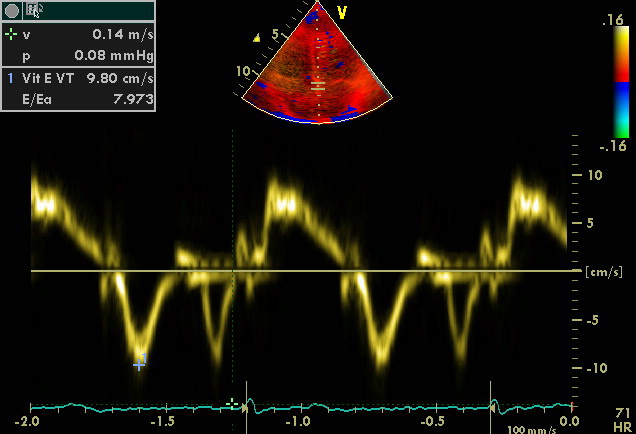

...en mode Doppler tissulaire: au niveau de certaines zones d'intérêt (implantation de l'anneau mitral sur le septum ou sur la paroi libre), la mesure des vitesses tissulaires permettent d'évaluer la performance cardiaque en estimant de manière semiquantitative les pressions de remplissage VG. Le rapport des vélocités sanguines aux vélocités tissulaires permet une estimation fiable des pressions de remplisage ventriculaire gauche. Un ratio E/Ea supérieur à 12 indique une pression télédiastolique VG élevée (Ea= vélocité tissulaire au niveau de l'anneau mitral, E= vélocité sanguine au niveau transmitral)

sujet volontaire sain PTDVG non élevée E/Ea = 8